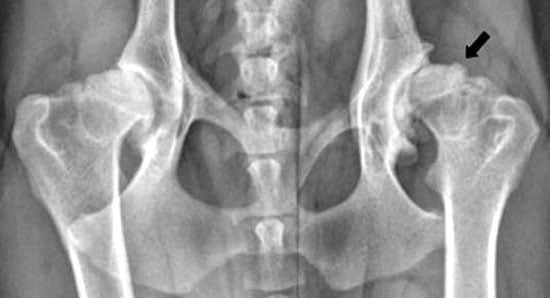

RADIOGRAFÍAS: Las radiografías son esenciales para confirmar el diagnóstico y evaluar la gravedad de la displasia. Estas imágenes permiten observar cómo encajan las estructuras óseas en la articulación.